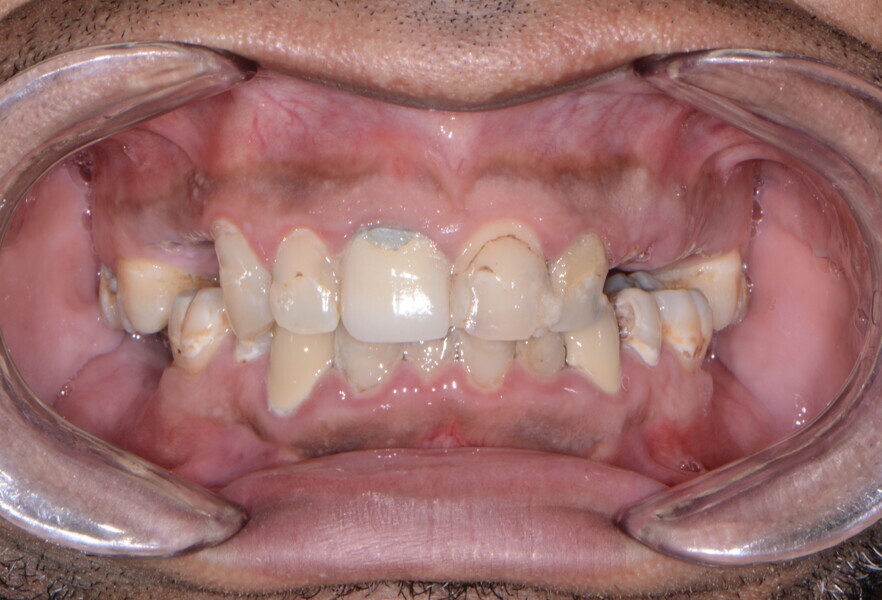

Fig. 5: Pre-op panoramic view.